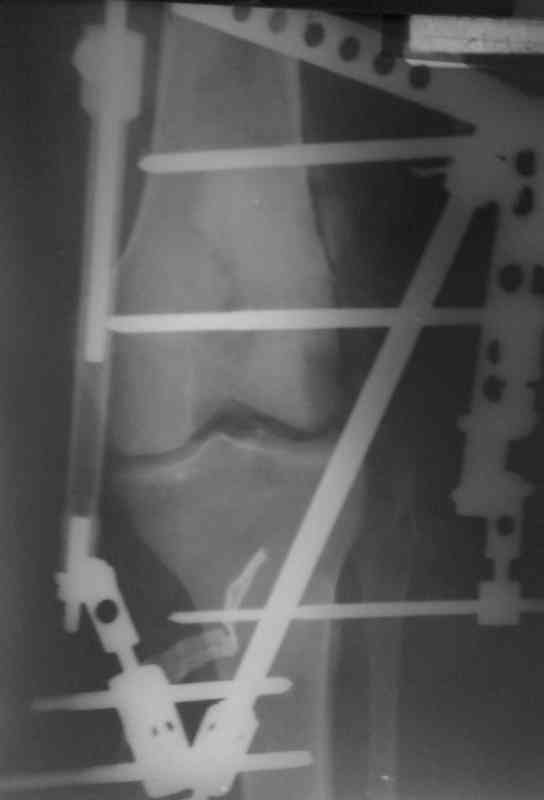

Доктор Castro,

На ренгенограмме хорошая аппозиция костей коленного сустава, но надколенник находится подозрительно высоко, поэтому необходимо убедиться в отсутствии повреждения связки надколенника.

Аппарат внешней фиксации удаляется в 6-7 недель,

предпочтительно под общим обезболиванием, во время

удаления проверяется стабильность и амплитуда движения в коленном суставе с редрессацией.

При пользовании стержневых наружных фиксаторов,

надо придерживаться правила проведения стержней подальше от зоны, на бедре лучше накладывать стержни косо передне-латерально, между брюшками прямой и vastus lateralis, а на голени по передне-медиальной поверхности большеберцовой кости, где отсутствует мышцы, иначе

восстановление движения в суставе тяжелее из-за

прошитых мышц спицами или стержнями аппарата.

Снимки прошлых публикации из моего Power point